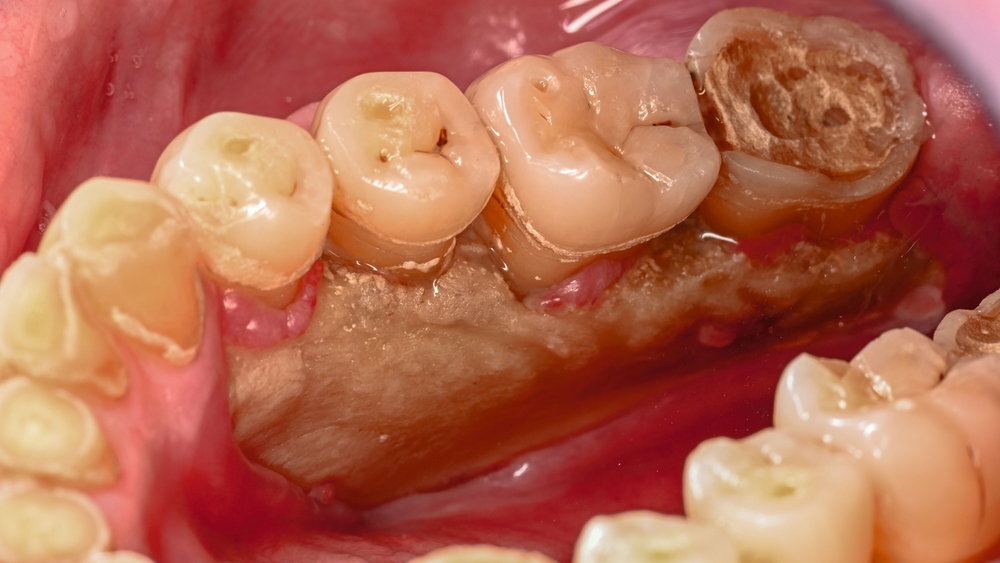

Der Patient stellte sich mit freiliegendem Knochen in Regio 43 bis 47 und mehreren gelockerten Zähnen vor. 45 und 46 waren devital. Als klinische Besonderheit fiel auf, dass sich innerhalb der Nekrosezone kleinflächige Weichgewebsareale darstellten, die in dieser Form bei klassischen Osteonekrosen üblicherweise nicht beobachtet werden. Eine klassische Vincent-Symptomatik bestand nicht. Drei Wochen zuvor war eine Herpes-Zoster-Infektion dermatologisch diagnostiziert und zunächst stationär behandelt worden. Der Patient erhielt eine intravenöse, antivirale Therapie, die bei Entlassung oralisiert wurde.

Zum Zeitpunkt der Erstvorstellung in der kieferchirurgischen Ambulanz zeigten sich keine klassischen Herpes-Zoster-Effloreszenzen im Gesicht. Eine antiresorptive Therapie oder Bestrahlung lag nicht vor, sodass eine Herpes-Zoster-assoziierte Osteonekrose im Sinne einer Ausschlussdiagnose festgestellt wurde. Anamnestisch bestand ein gut eingestellter Diabetes mellitus Typ 2 als potenziell immunkompromittierende Grunderkrankung. Die Knochenszintigrafie zeigte eine deutliche Stoffwechselsteigerung im betroffenen Bereich, vereinbar mit einer infizierten Osteonekrose.

In den publizierten Fallserien war der Unterkiefer häufiger betroffen als der Oberkiefer (Verhältnis etwa 3,5 zu 1). Der Krankheitsbeginn liegt meist zwischen der zweiten und der vierten Woche nach den Hauteffloreszenzen, kann aber auch verzögert auftreten [Mintz, 1992; Badjate, 2009]. Typisch ist ein einseitiger Verlauf entlang der betroffenen Nervenäste, auch mit spontaner Zahnexfoliation, freiliegendem Knochen und (manchmal) persistierender Neuralgie. Differenzialdiagnostisch müssen die MRONJ, die Osteoradionekrose und die bakterielle Osteomyelitis ausgeschlossen werden. Wenn diese Ursachen fehlen und eine zeitlich assoziierte Herpes-Zoster-Infektion besteht, ist die Diagnose einer HZ-assoziierten Osteonekrose naheliegend [Aghaloo, 2017].